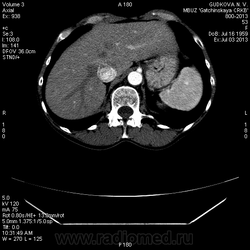

В артериальную фазу - интенсивное накопление контраста, как раз в области этого расширения, в 4-5 сегментах печени.Выше и ниже - идет неизмененная НПВ, без контраста (фаза артериальная!) В венозную фазу - небольшая гиперденсная зона перикавально в печени - и все.

Контрастированная нижняя полая сбила с толку. Кстати, там и v.porta есть:)

А образование, про которое пишут узисты (1,2 в диаметре) я нашел! Это - киста мелкая(контраст не копит совершенно)

Да, это нижняя полая вена.

Мелкую кисту в правой доле печени (S6) я нашел. Ее нет на представленных сканах(выложил то, что меня смутило), но, думаю, именно ее описывают УЗИсты. И размеры совпадают, и гипоэхогенность характерна для кисты.